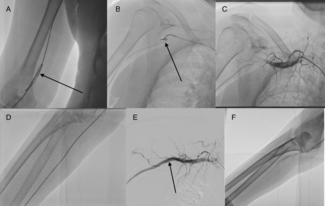

A 66-year-old male Jehovah’s Witness arrived at the emergency room having experienced typical persistent angina. Upon arrival, he was hemodynamically unstable.

A 66-year-old male Jehovah’s...